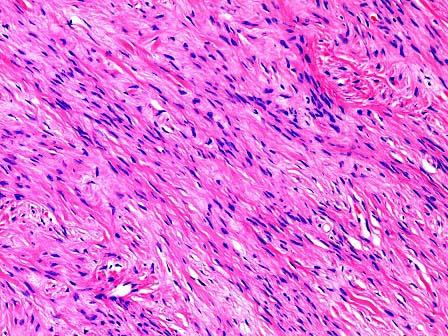

问题 女性,45岁,一年,腹水3月加重1月,妇检扪及左侧附件包块,质硬,行左卵巢切除送检。见卵巢一结节。直径3cm,切面灰白,略呈漩涡状。镜下见大量波浪状的胶原性结缔组织,小的梭形细胞排列成紧密的漩涡“席纹状”(如图),应诊断为 ( )

选项 A.卵巢纤维瘤 B.卵巢卵泡膜瘤 C.卵巢腺纤维瘤 D.卵巢粒细胞瘤 E.卵巢平滑肌瘤

答案 A